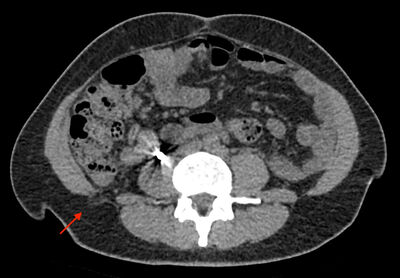

Hún leitaði í fyrstu til lýtalæknis og vaknaði þá grunur um fituæxli (lipoma). Fengin var ómskoðun af kviðvegg og hægri síðu þar sem lýst var kviðsliti í hægri síðu með rúmlega 1 cm kviðslitsopi og um 5 cm kviðslitssekk. Til nánari kortlagningar var gerð tölvusneiðmynd af kvið sem sýndi lendarkviðslit sem gæti samrýmst Petit-kviðsliti og innihélt fituvef frá aftanskinu (mynd 2). Í framhaldi var henni vísað til skurðlæknis á stofu en vegna óvanalegrar staðsetningar var henni vísað áfram á göngudeild kviðarholsskurðlækninga á Landspítala. Þar gaf hún söguna sem lýst er að ofan. Við skoðun var enga fyrirferð að finna á hægri síðu eða baki.

Mynd 2.Tölvusneiðmynd af kviðarholi sýnir neðra lendarkviðslit sem inniheldur fituvef frá aftanskinu.